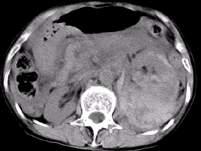

问题 男,37岁,左腰部疼痛伴血尿,有外伤史,CT检查如图所示,下列说法错误的是 ( )

选项 A、考虑为肾挫伤 B、考虑为肾包膜下出血 C、左侧肾实质增厚,其内密度不均,可见大片状不规则的高密度影 D、腹腔内可见较高密度的积液 E、左侧肾影增大模糊,肾轮廓消失

答案 B